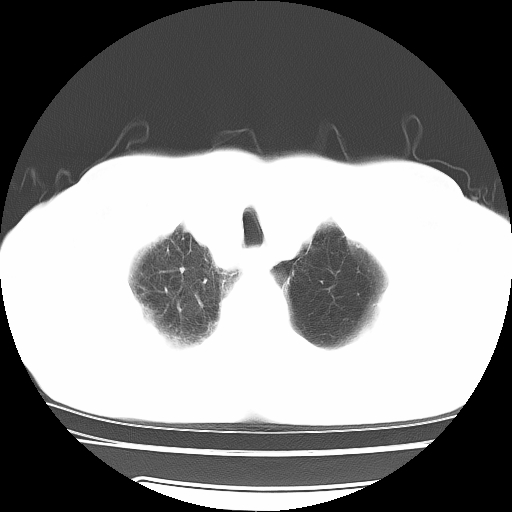

男,71岁,咳嗽,气喘10年,再发并咯血.胸片见气胸

考虑  左肺中心型肺癌伴阻塞性肺炎,肺不张,纵膈淋巴结肿大。慢支炎,肺气肿,左侧气胸肺压缩5%

左侧中央型肺癌伴纵膈淋巴结转移。

左肺中心型肺癌伴阻塞性肺炎,肺不张,纵膈淋巴结肿大

1)考虑左肺中心型肺癌伴阻塞性肺炎、左肺下叶肺不张、左侧肺气肿,纵膈淋巴结转移。2)左侧气胸(肺组织压缩约5%)。

左肺中心型肺癌伴阻塞性肺不张、肺气肿 。

1)考虑左肺中心型肺癌伴阻塞性肺炎、左肺下叶肺不张、左侧肺气肿,纵膈淋巴结转移。2)左侧气胸。